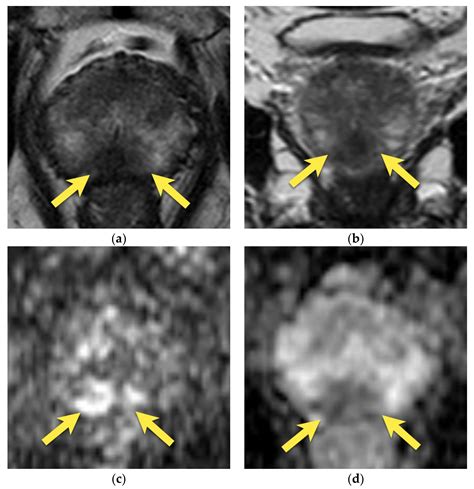

• Multiparametric MRI (mpMRI): This technique combines multiple MRI sequences, including T2-weighted imaging, diffusion-weighted imaging (DWI), and dynamic contrast-enhanced (DCE) imaging, to provide a comprehensive evaluation of the prostate.

• Fusion Biopsy: This technique combines MRI images with real-time ultrasound guidance to perform targeted biopsies, improving the accuracy of cancer detection.